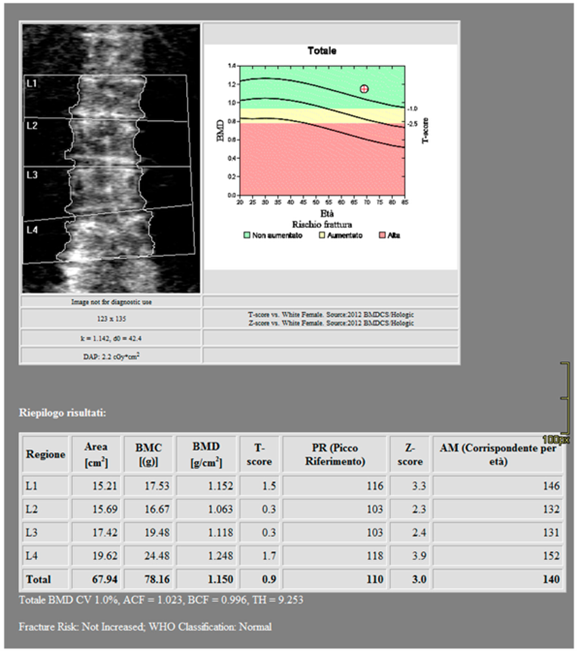

骨質密度檢查,了解自己的骨頭年齡

目前最常用的檢查是 骨質密度檢查 (DXA),通常會測量腰椎和髖部。報告會給出一個「T 值」:

- 大於 -1:骨質正常

- -1 到 -2.5:骨質減少(骨鬆前期)

- 小於 -2.5:骨質疏鬆

(圖3.)DXA 量測範例(腰椎)

來源:Stoppino LP, et al. J Imaging. 2024;10:104. CC BY 4.0。DOI:10.3390/jimaging10050104